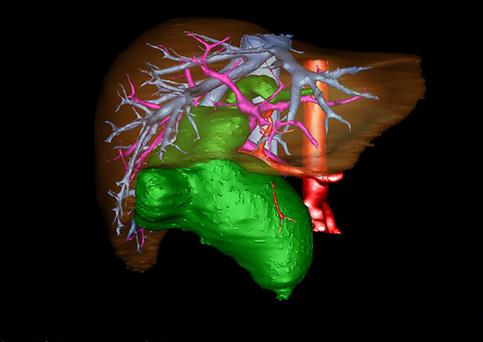

图11:先天性胆管扩张症梭状型三维重建虚拟肝脏、胆道显像

a 图为术前二维CT扫描图像,箭头指示肝内胆管扩张;b 图为CT经多平面重组技术(MPR)所得的重建图像,可粗略地判断病变胆管的位置;c 图示术前Hisense CAS三维重建清晰显示胆管的病理形态及其与肝内三套血管系统的解剖关系;d 图示胆道系统与其伴行的门静脉系统的空间解剖关系;e 图为胆道系统立体形态,箭头处指示迷走胆管,源自肝脏直接汇入胆总管。术前规划先将迷走胆管与肝总管吻合成形,再行肝总管空肠Roux-en-Y吻合术。